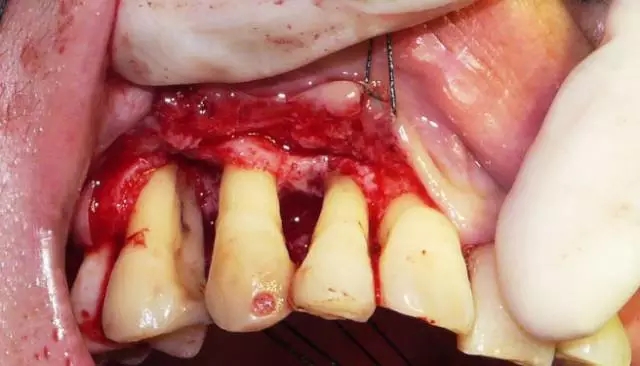

術(shù)中徹底清除后的牙根面

翻開腭側(cè)粘骨膜瓣,去除炎性肉芽組織,根面用牙周銼清理后,顯示明顯的骨下袋和干干凈凈的根面。在這樣的骨下袋里植骨效果是非??煽康摹?/span>